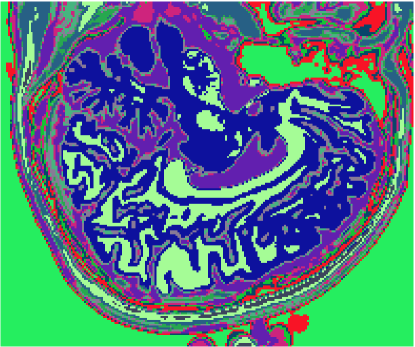

As figuras 2 (banda 0), 3 (banda 1) e 4 (banda 2) mostram a fatia 97 de um volume de imagens sagitais com 181 fatias e 0% de ruído, ponderadas em PD (densidade de próton), T1subscript𝑇1T_{1} e T2subscript𝑇2T_{2}, enquanto a figura 5 ilustra a composição colorida R0-G1-B2 da mesma fatia. Pode-se notar no topo do crânio, na parte inferior das imagens, a presença de artefatos, que podem ser resultantes de erros no simulador, mas que não são prejudiciais à análise, uma vez que, neste trabalho, não é dada ênfase à análise anatômica.

Refer to caption

Figura 5: Composição colorida R0-G1-B2 das imagens da fatia 97 ponderadas em PD, T1subscript𝑇1T_{1} e T2subscript𝑇2T_{2}